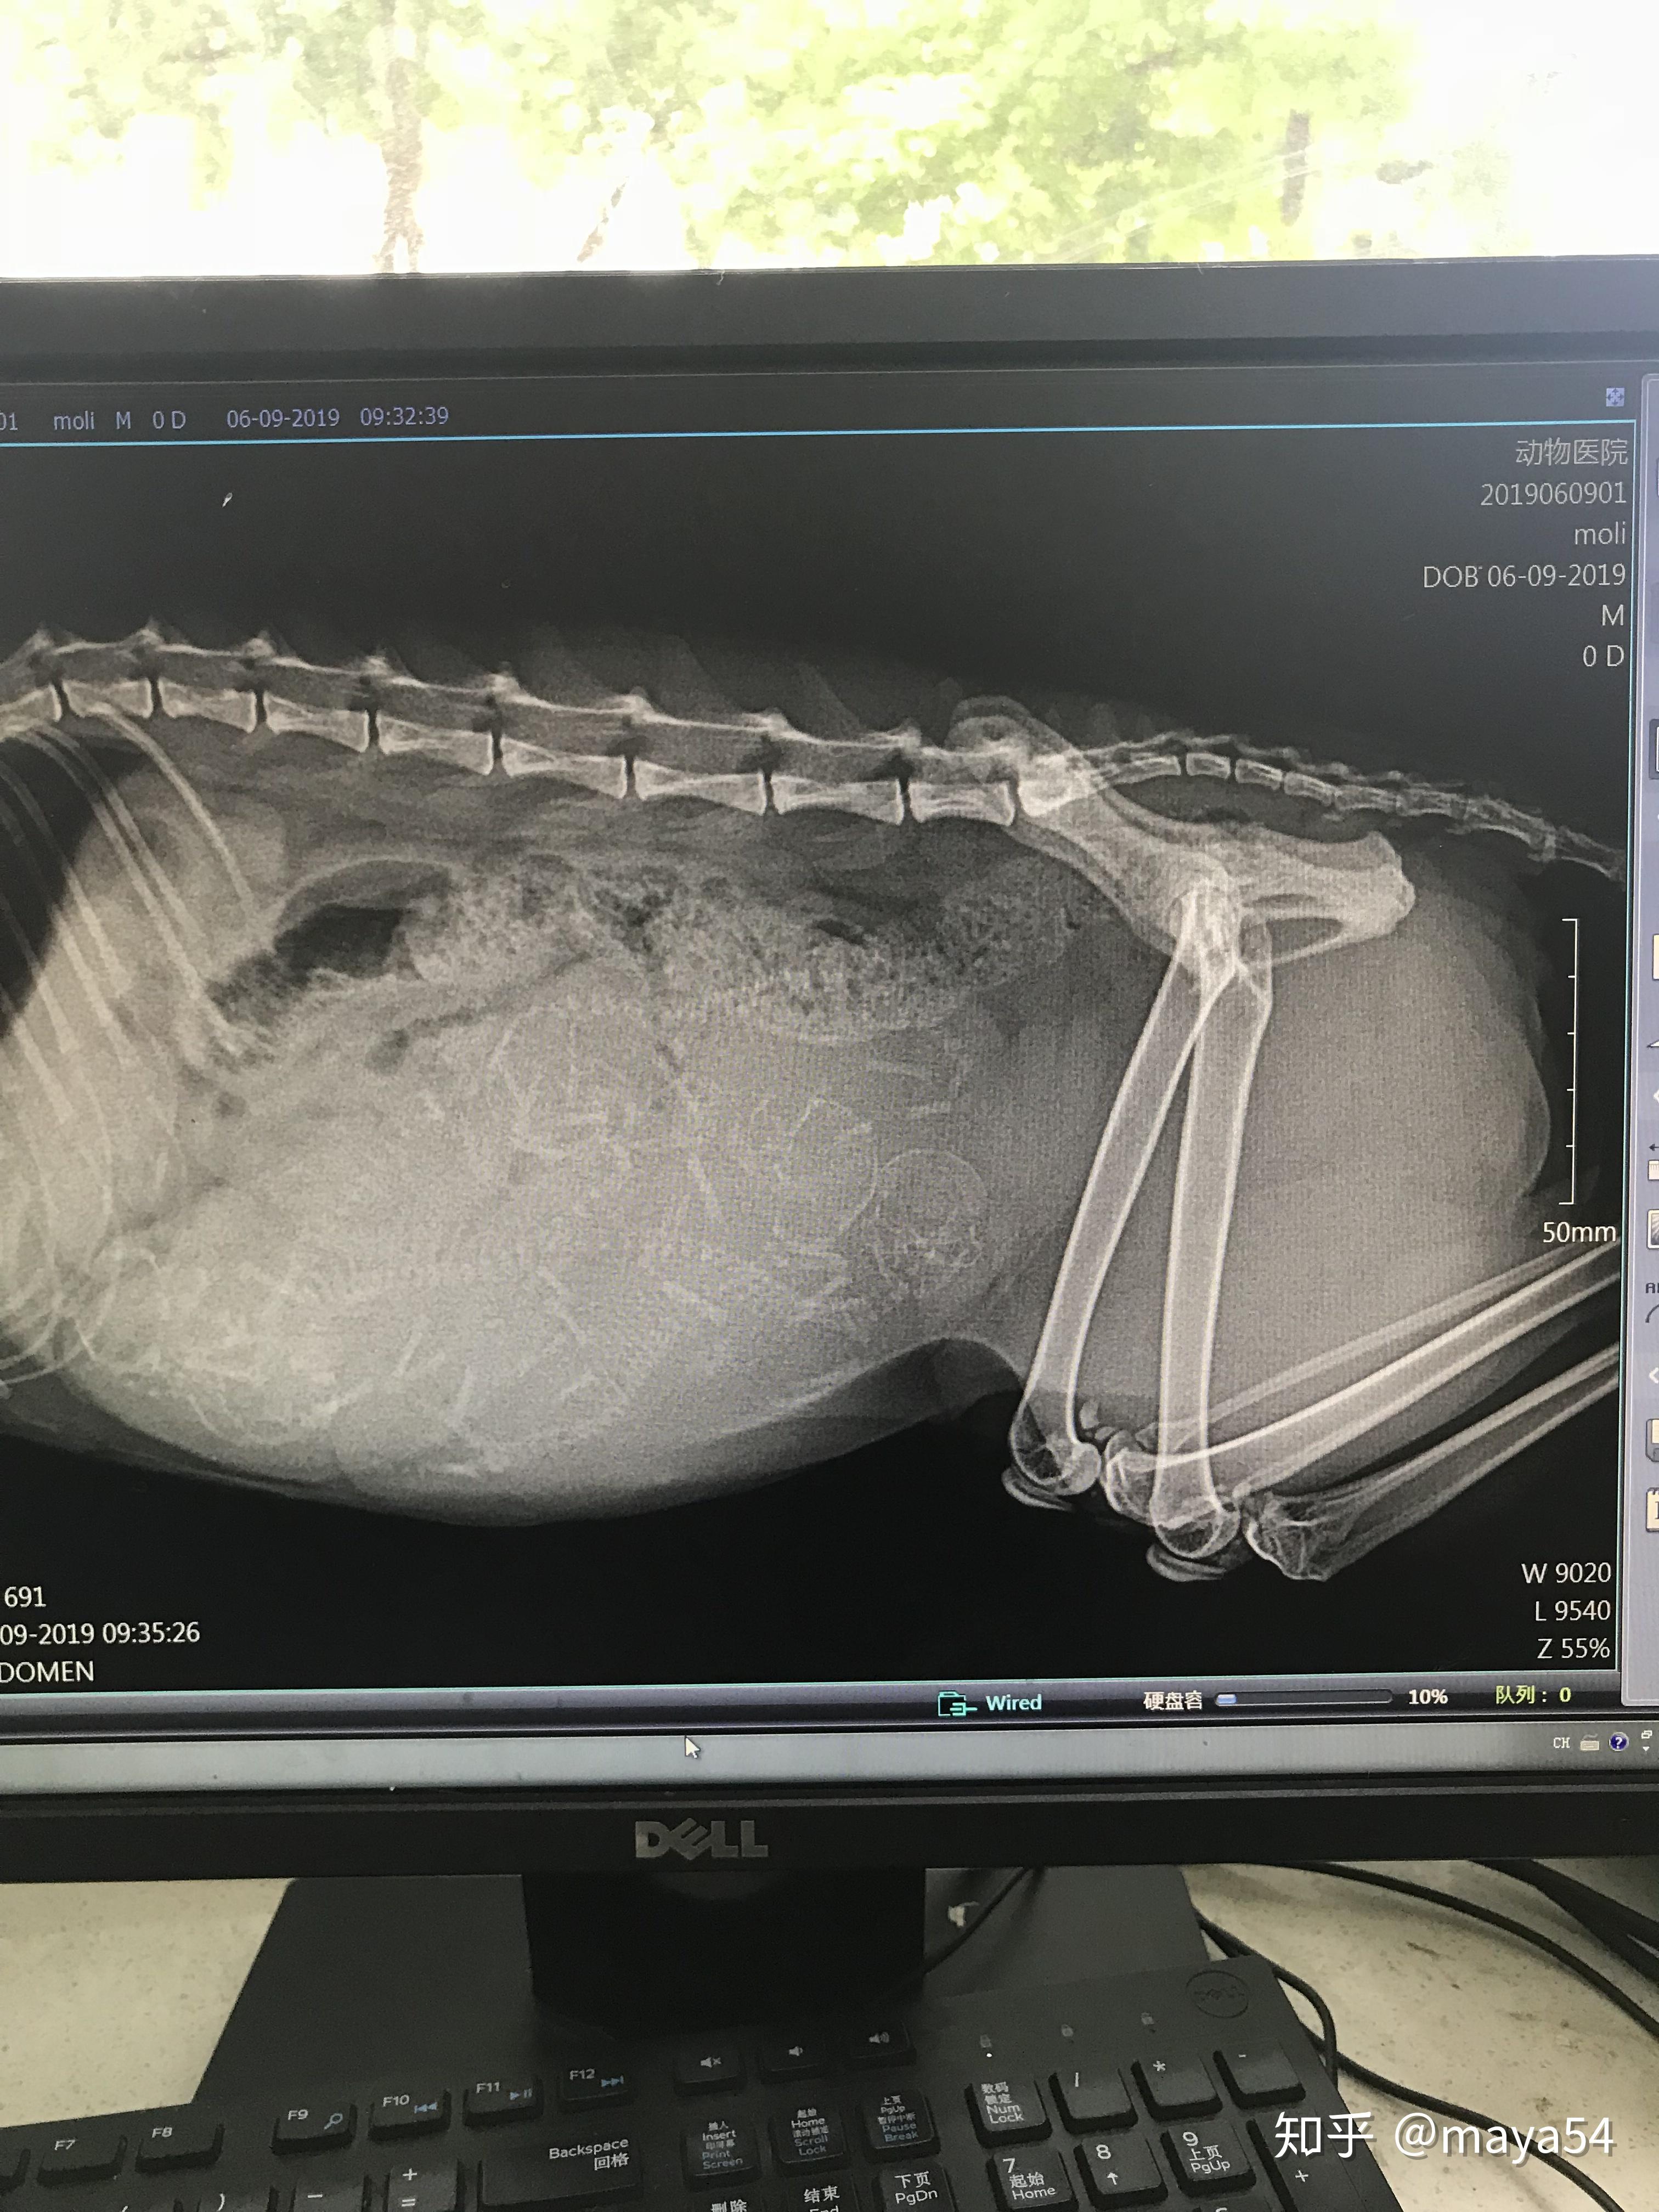

6月9日,我已经按奈不住去医院照了x光,可能还是太早看不太清,医生说三